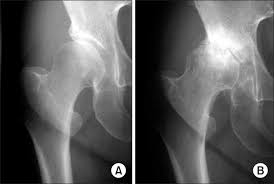

In human anatomy, the muscles of the hip joint are those muscles that cause movement in the hip. In this article we describe the hip and thigh muscles. Calcium, iron, and energy in the form of fat. Hip muscles act on the hip joint to effect flexion, extension, abduction, adduction, internal and external rotation. Guinea pig body parts diagram. Female hip and leg muscles labeled posterior view, 3d rendering. The sacrum bone is almost always noticeable, no matter what the body type right: The hip joint is a ball and socket synovial type joint between the head of the femur and acetabulum of the pelvis. Most modern anatomists define 17 of these muscles, although some additional muscles may sometimes be considered. To see a muscular system diagram from muscle diagram anatomy practice health and physical education musculoskeletal system. © productive fitness products inc. The human leg, in the general word sense, is the entire lower limb of the human body, including the foot, thigh and even the hip or gluteal region. Muscles, connected to bones or muscles that act on the lower limb cause movement at the hip, knee and foot joints.